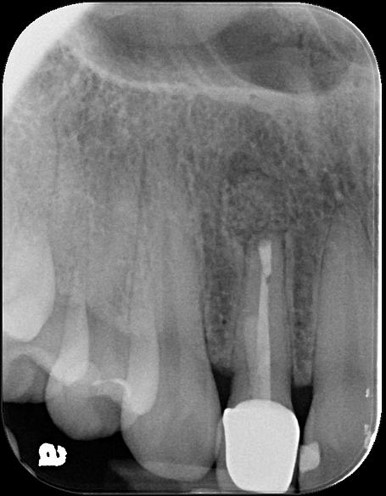

手術後根尖片

1年後根尖片追蹤